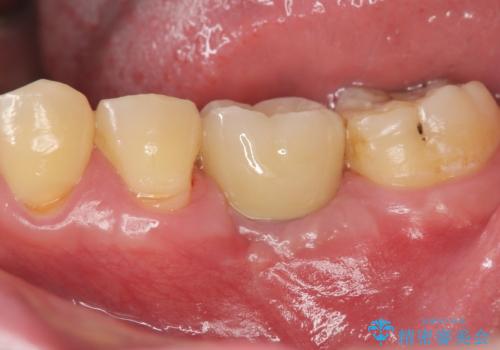

[ インプラント治療 ]失った奥歯を回復したい

![[ インプラント治療 ]失った奥歯を回復したいの症例 治療後](https://seimitsushinbi.jp/wp/wp-content/uploads/2021/11/7d51b0ec04f819febabdd26c9bfb7954-500x350.jpg?v=1637928867)